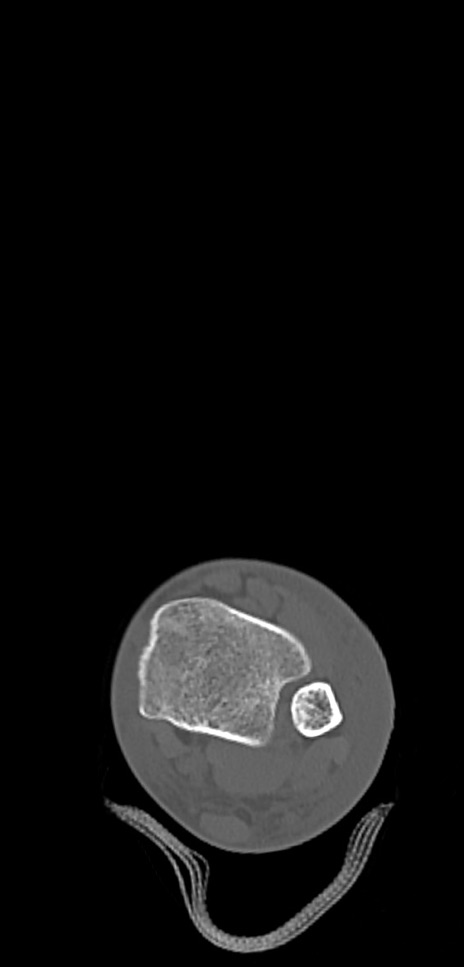

症例37 左足関節CT(横断像)

左足関節CT